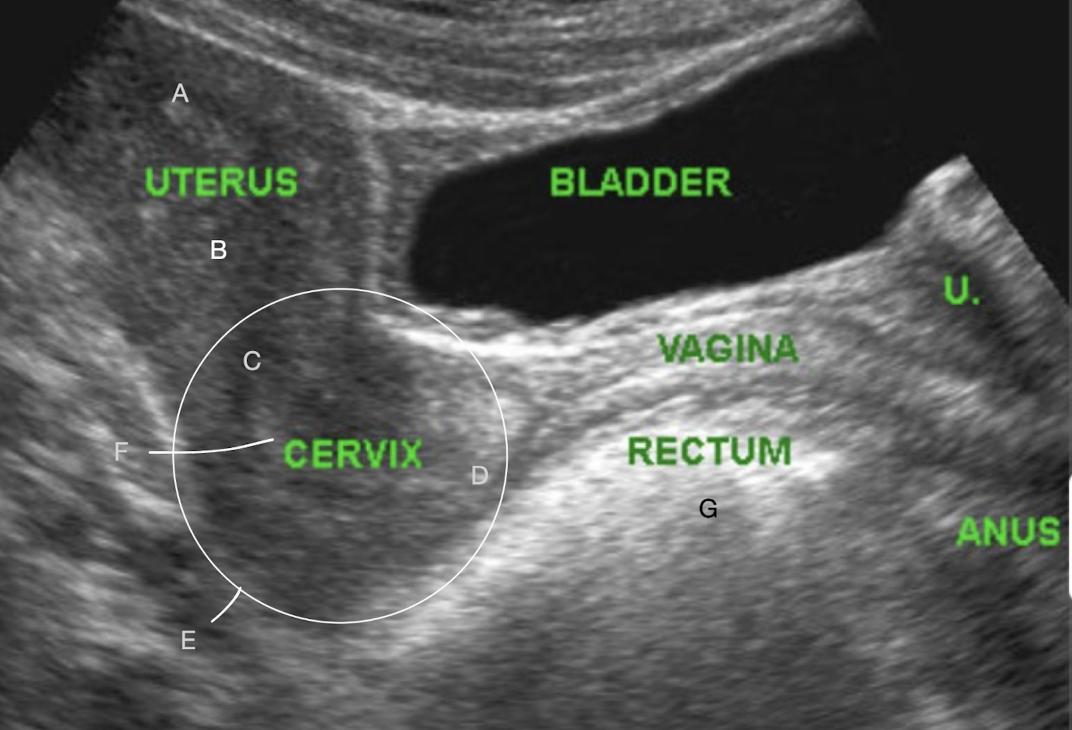

SONO: vagina, cervix, uterus

A?

B?

C?

D?

E?

F?

G?